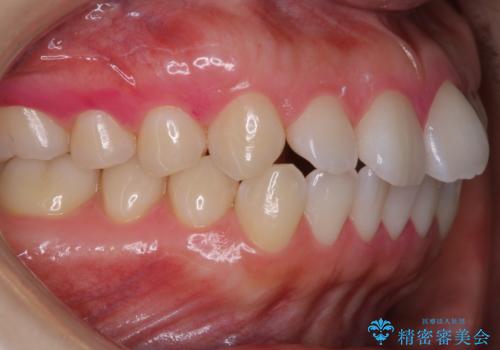

タバコによるヤニをPMTCで除去

担当医 歯科衛生士